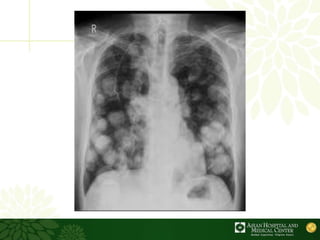

. Pada parenkim paru nodul metastasis soliter dan multipel cenderung didapati pada bagian perifer dan diperkirakan berasal dari penyebaran hematogen. Metastatic Breast Cancer is Constantly Changing Find Out Why Its Important to Act Early. Metastasis Penyebaran Metastasis adalah penanaman tumor yang tidak berhubungan dengan tumor primer.